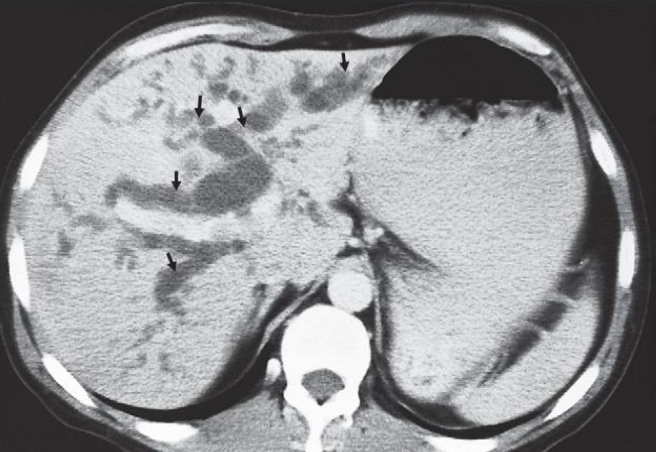

The patient had carcinoma of the bronchus.

CT scan of liver metastases. There are a large number of low density lesions in both lobes of the liver, which show enhancement around their edges.

LIVER METASTASIS

Imaging examination CT scan